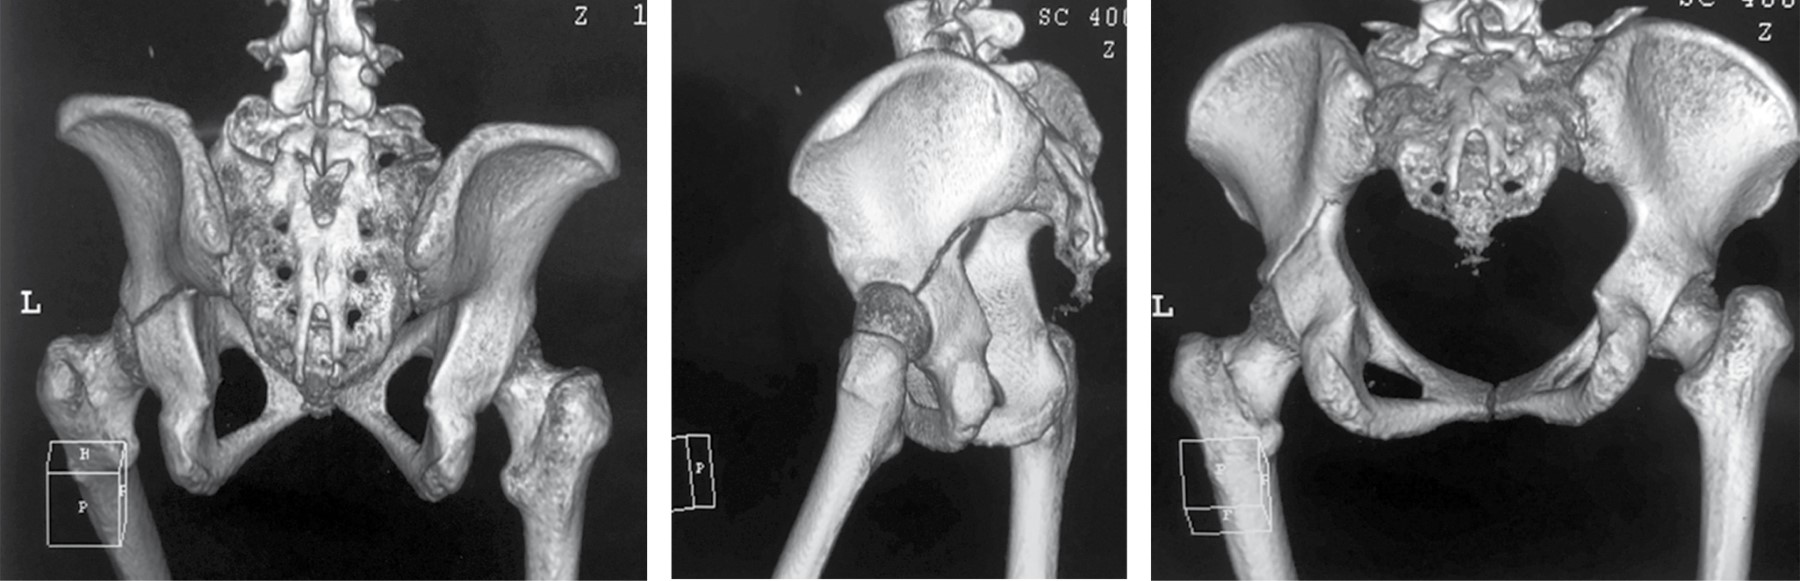

Femenino, de 38 años de edad, con antecedente de accidente automovilístico, con trauma e impacto indirecto en rodilla izquierda, causando dolor y limitación funcional de la extremidad pélvica izquierda; fue evaluada en urgencias sin lesiones multisistémicas asociadas. Se realizó toma de las proyecciones radiográficas simples y tomografía axial computada de pelvis, con reconstrucción en 3D (Figura 1). Se observó pérdida de continuidad ósea a nivel de línea iliopectínea, llegando al diagnóstico de fractura simple de acetábulo izquierdo AO 62-A2.2 que involucra la columna posterior.30

Figura 1